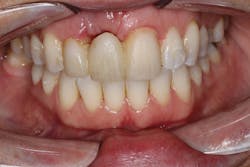

• site development to increase hard and soft tissue for pontic sites in fixed bridge prosthetics (figures 9–14);• correcting bone defects impinging upon anatomical structures after tooth extraction, such as oroantral communication (figure 18); and